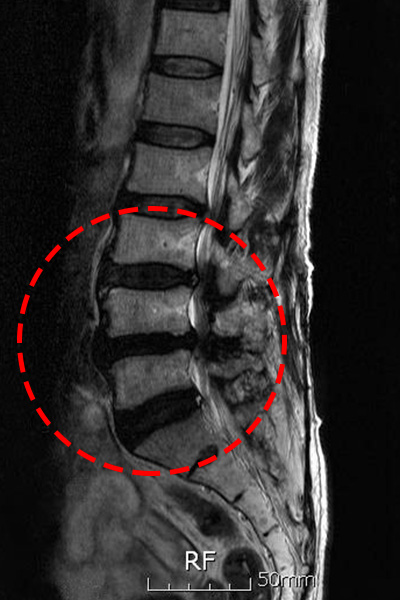

① 허리 디스크(추간판 탈출증)

척추뼈 사이에는 탄력 있는 쿠션 역할을 하는 '추간판'이 있습니다. 이 디스크는 외부의 단단한 섬유륜과 내부의 부드러운 수핵으로 구성되어 있습니다. 나이가 들면서 디스크 내 수분 함량이 감소하면 탄력성이 떨어지게 되고, 무거운 물건을 들거나 갑작스런 움직임이 가해질 때 섬유륜이 파열되어 수핵이 밖으로 튀어나옵니다. 이것이 신경을 압박하면서 심한 허리 통증과 다리 저림 증상이 발생합니다.